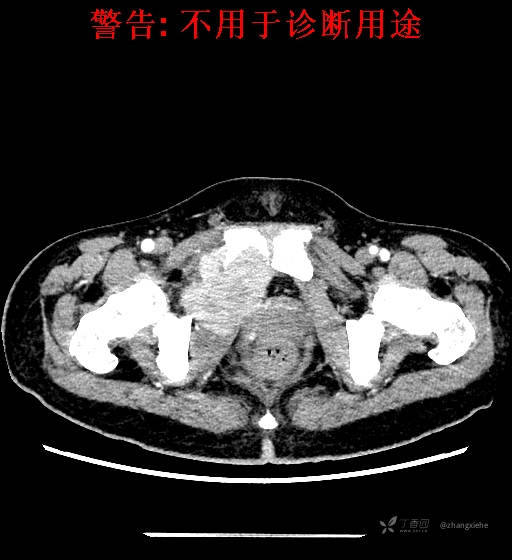

现病史:患者2022-02-07在市中医院体检发现右肺占位,胸部CT示:右肺下叶基底段见一不规则软组织密度影,增强扫描呈轻中度强化,可见血管贴边征。当时无任何不适。2022-02-24于省肿瘤医院行纤支镜检查阴性,痰检未找到癌细胞。经皮肺穿刺细胞学检查找到高度癌疑细胞,病理示:右下肺穿刺考虑神经内分泌癌。免疫组化结果:CgA(-)、CD56(-)、Syn(+)、CK广谱(-)、p40(-)、P63(少量+)、TTF-1(-)、Ki-67(+,40%)、NapsinA(-)、Calcitonin(-)、TG(-)。ECT示:全身骨扫描未见明确骨转移征象。患者出现贫血且逐渐加重、低蛋白血症,予人促红素注射液、精蛋白重组人胰岛素混合注射液、人血白蛋白对症处理,效果不明显,病情加重,右髋出现疼痛,不能行走。2022-03-04转院南大二附院进一步治疗,2022-03-20行右侧髂骨穿刺活检术,术后病理结果示:考虑软组织透明细胞肉瘤。免疫组化示:瘤细胞Vim(+)、NSE(+)、S-100(+)、SOX10弱(+)、Melan-A(+)、TFE-3部分弱(+)、CK(-)、MyoD1(-)、Desmin(-)、HMB45(-)、CD34(-)、CD68(-)、CR(-)、Ki-67约15%(+)。特殊染色示:网状纤维染色(-)、PAS(±)。

2022-03-05血常规示:血红蛋白:64g/L,生化示:白蛋白20g/L。骨髓涂片细胞学检查示:骨髓增生明显活跃,粒红比减低。粒、红、巨三系增生明显活跃。粒系伴成熟障碍。髓片浆细胞较易见,占7%。粒系增生明显活跃,核明显左移,可见巨幼样变及核浆发育不平衡。PET-CT示:1.右肺下叶软组织肿块、右侧耻骨下支及耻骨联合处骨质破坏伴软组织肿块形成,FDG代谢均异常增改,考虑恶性病变,建议病理检查;右侧髂血管旁、双侧腹股沟淋巴结反应性增生,建议随访。2.多浆膜腔(双侧胸腔、心包腔、盆腔)少量积液。3.全身骨骼FDG代谢弥漫增高,考虑骨髓反应性增生。4.大小肠条片状FDG代谢增高,考虑生理性摄取。5.右侧上颌窦面膜下囊肿,脑部FDG代谢未见明显异常。6.C7-T1层面后纵韧带钙化。患者乏力加重,卧床不起,不能承重,大小便不顺畅,转院至我院。门诊拟“1.右肺占位并右侧骨盆转移2.低蛋白血症3.中度贫血 4,血糖升高(原因待查)”收入住院。患者发病以来,无胸闷、胸痛,无呼吸困难,偶咳嗽,无咳血,饮食、睡眠欠佳,2个月之内体重减轻约10kg。